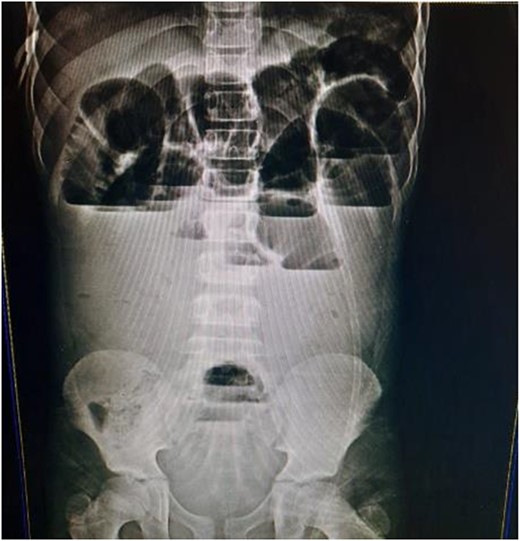

A 9-year-old child presented at the emergency department at our hospital after 4 days with symptoms of small bowel obstruction, including diffuse abdominal pain, nausea, vomiting, constipation and abdominal distension. His past medical history was not significant, and he had no surgical history. The abdomen was breathing, smooth, tender without rebound tenderness; no signs of peritonitis and appendicitis were appreciated. His rectal examination was unremarkable. A pulse rate of 100/min. The abdominal X-ray showed multiple air-fluid levels (Fig. 1). A diagnosis of small bowel obstruction was made; the patient underwent intravenous fluid therapy and nasogastric tube insertion before undergoing surgical intervention that involved midline incision and exploratory laparotomy. During surgery, the small intestine was found to be dilated and congested, with an MD located 30 cm from the ileocecal valve, associated with a fibrous band connected to the anterior abdominal wall at the umbilicus. The small intestines were wrapped around the fibrous band, causing the obstruction (Figs 2 and 3). The intestines were released, the MD and the band were excised with end-to-end anastomosis and a pelvic drain was inserted. The patient was discharged. By follow-up, the patient showed no evidence of complications.

The fibrous band connected to the umbilicus, where the small intestines were wrapped around the band.

MD is the most common congenital malformation in the lower portion of the small intestine [1, 2]. The cause of this diverticulum is the vitelline duct, which normally connects undeveloped gut to the yolk sac that will atrophies during 5th–7th week of pregnancy [3]. When the vitelline duct did not atrophy completely then it develops into a true diverticulum, which makes up 2% of population [2]. Most people with diverticulum are asymptomatic [2]. Symptoms appear usually during the 1st year of life, with the possibility of their appearance during childhood [2]. These symptoms include rectal bleeding or intestinal obstruction [4]. Our case presented with small intestinal obstruction and we confirmed it through abdominal X-ray. The intervention was surgical that involved midline incision. During the surgery, it was revealed that there was the MD, located 30 cm from ileocecal valve and bloody supplied by yolk arteries [2, 4]. Intussusception or inversion of the MD into the ileum or cecum, or the existence of the fibrous band that entraps the vascular supply of the small bowel underneath it and may lead to strangulation, or wrap the small intestines around the fibrous band from MD to the umbilicus [4].That happens commonly for people who have diverticulum with obstruction symptoms [4]. The fibrous band is a remnant of right and left yolk arteries [4]. The anatomical structure for the diverticulum of length and base is important factor for rotation around the band thus occurrence of obstruction [6]. In other cases, reported pre-operate diagnosis is rare by 4% of their cases. MD can be diagnose by ultrasound when there are complications and it is not specific [7]. Arteriography and technetium pertechnetate scanning are good for diagnosis in case with bleeding or ectopic gastric mucosa [8].